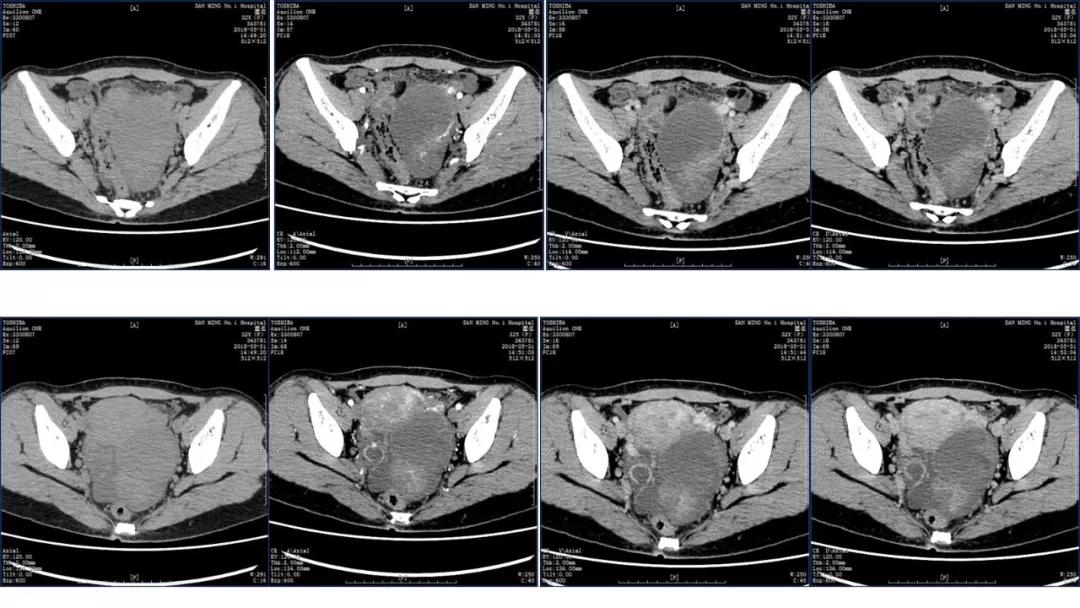

病例4 女,32岁,以“月经量增多伴经期延长半年。”

缘于患者入院前半年无明显诱因出现月经量增多,卫生巾由原来3包余增至5包不等,伴血块,经期由原来7天延长至10-15天不等,无痛经,无月经周期改变,无阴道异常排液,无畏冷、发热,无头晕、乏力等不适,未重视,未诊治。期间症状持续。2月前就诊我院,查彩超示:“子宫体大小约5.7*5.3*4.6cm,内膜厚约0.6cm,回声不均,左卵巢旁探及大小约4.2*3.5cm低回声区。”建议治疗,患者及家属表示考虑。期间症状持续,今就诊我科门诊,要求住院手术治疗,无腹痛等不适,门诊拟“卵巢囊肿”收住入院。既往史:2007年剖宫产一次,术顺。月经史:15 7/25 lmp2018.05.14,量中,无痛经。婚育史:已婚,1-0-3-1,末孕2007年剖宫产娩一男婴,儿子及丈夫体健。个人史、家族史均无特殊。

TCT:见少许非典型细胞;(2018.03.26)HPV:均阴性;

2018-05-28 血常规五分类:白细胞 8.2(10^9/L),中性粒细胞百分比 65.80(%),血红蛋白 108(g/L),血小板 359(10^9/L);凝血功能、肝肾功能电解质、尿常规大致正常;乙肝两对半加丙肝均阴性;

尿HCG 阴性;RPR 阴性,TPPA 阴性,HIV抗体 阴性;

CA125 335.5(U/mL);2018-05-30 彩超:子宫宫体大小约5.6㎝×6.3㎝×4.9㎝,形态正常,宫壁回声欠均,内膜厚约1.8cm,回声不均。CDFI:子宫内未见明显异常彩色血流信号。左附件区探及一混合回声团块,大小约9.8㎝×7.9㎝,CDFI:其实性部分可见少许彩色血流信号。右附件区未见明显包块回声。

病理:卵巢子宫内膜样癌